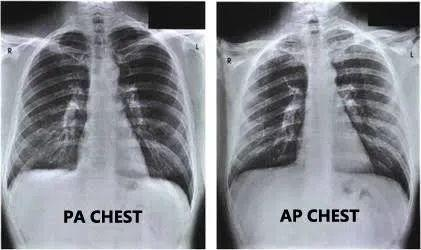

胸片的类型

从数据集中,可以找到三种类型的图像,PA、AP和Lateral(L)。L的很明显,但X光的AP和PA视图有什么区别?简单地说,在拍X光片的过程中,当X光片从身体的后部传到前部时,称为PA(后-前)视图,在AP视图中,方向相反。

通常,X光片是在AP视图中拍摄的,但是一个重要的例外就是胸部X光片,在这种情况下,最好在查看PA而不是AP,但如果病人病得很重,不能保持姿势,可以拍AP型胸片。

由于绝大多数胸部X光片都是PA型视图,所以这是用于训练模型的视图选择类型。